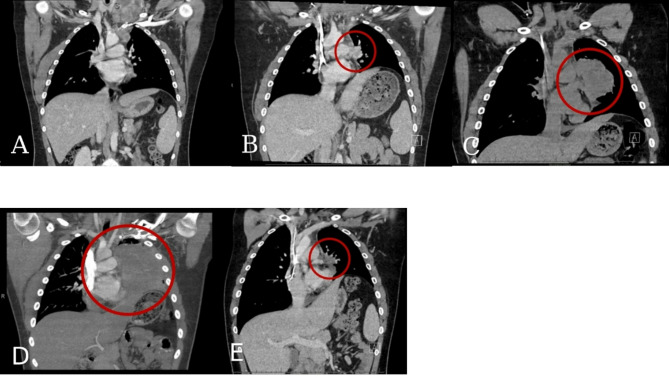

我们报告了一例起源于头部和颈部的广泛而庞大的儿童转移性黑色素瘤,该病例对抗程序性细胞死亡(PD-1)抑制和巩固的个性化超分割立体定向适应性放疗(PULSAR)联合治疗有明显反应。手术切除颈部后,患者最初接受抗pd -1和抗细胞毒性t淋巴细胞相关蛋白4 (CTLA-4)双检查点阻断免疫治疗,但很快疾病进展。他被转移到一种不同的抗pd -1免疫疗法,与酪氨酸激酶抑制剂联合使用PULSAR巩固局部治疗。这种联合治疗在纵隔的另一个部位进一步疾病进展之前达到了肿瘤缓解和无进展状态一年。由于其他方面疾病控制良好,继续进行单药抗pd -1免疫治疗,并对进展部位给予补救性PULSAR,再次导致肿瘤反应和6个月的无进展状态。在联合治疗后,没有较大部位的大体病变出现局部进展。本病例提示,PULSAR联合抗pd -1免疫治疗对小儿复发或难治性转移性黑色素瘤是有效的。临床试验号:不适用。

We present a case of extensive and bulky pediatric metastatic melanoma originating in the head and neck which markedly responded to combination therapy with anti-programmed cell death (PD-1) inhibition and consolidative personalized ultra-fractionated stereotactic adaptive radiotherapy (PULSAR). After surgical debulking with neck dissection, the patient was initially treated with anti-PD-1 and anti-cytotoxic T-lymphocyte associated protein 4 (CTLA-4) dual checkpoint blockade immunotherapy, but quickly had disease progression. He was transitioned to a different anti-PD-1 immunotherapy in combination with tyrosine kinase inhibitors in conjunction with consolidative local therapy using PULSAR. This combination therapy achieved tumor response and progression-free status for one year before further disease progression at a separate site in the mediastinum. Due to otherwise good disease control, single agent anti-PD-1 immunotherapy was continued and salvage PULSAR was administered to the progressive site, again resulting in tumor response and progression-free status for 6 months. None of the bulkier sites of gross disease had local progression after combination therapy. This case suggests that the synergistic effect of PULSAR and anti-PD-1 immunotherapy is efficacious for relapsed or refractory metastatic melanoma in pediatric patients. Clinical trial number: not applicable.